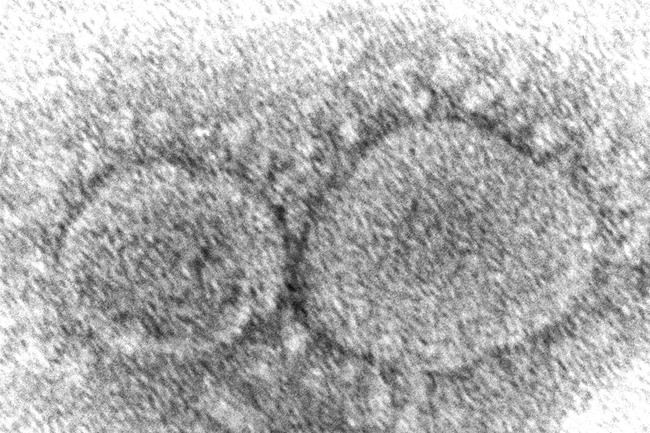

Evidence is mounting that having COVID-19 may not protect against getting infected again with some of the new variants. People also can get second infections with earlier versions of the coronavirus if they mounted a weak defence the first time, new research suggests.

How long immunity lasts from natural infection is one of the big questions in the pandemic. Scientists still think reinfections are fairly rare and usually less serious than initial ones, but recent developments around the world have raised concerns.